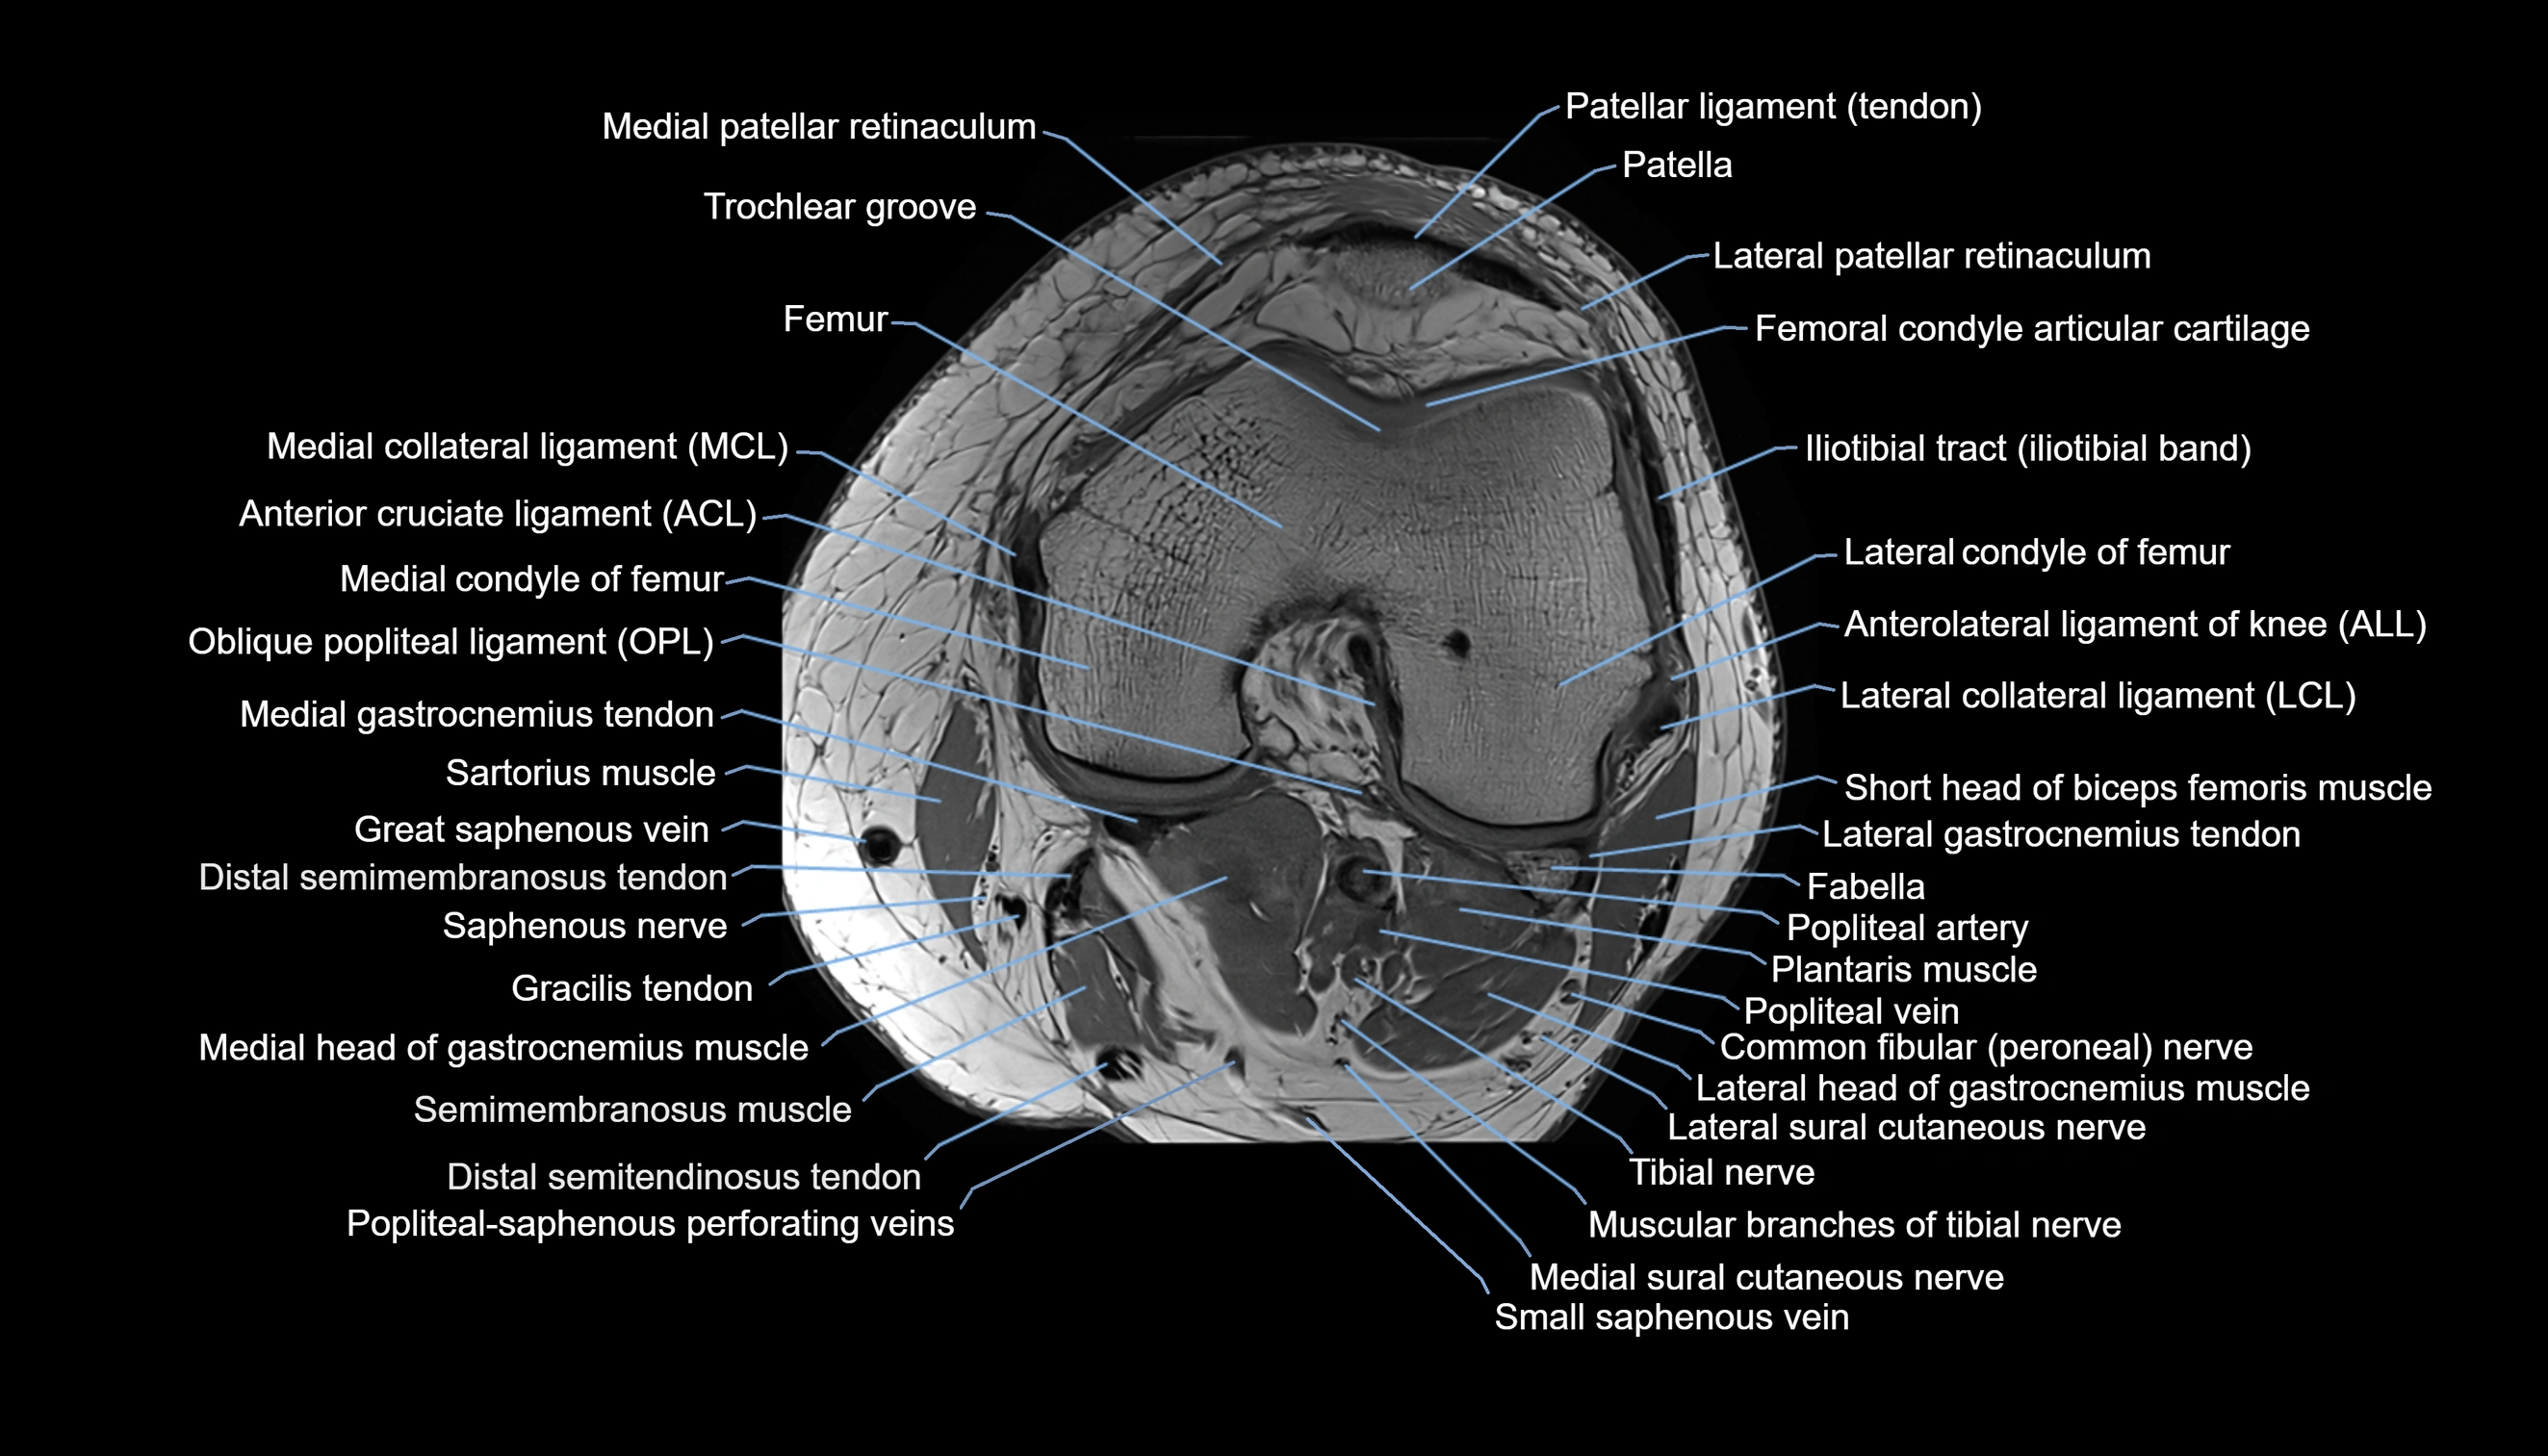

- Anterolateral ligament of knee

- Lateral collateral ligament

- Lateral patellar retinaculum

- Medial collateral ligament

- Medial patellar retinaculum

- Oblique popliteal ligament

- Popliteal artery

- Popliteal vein

- Tibial nerve